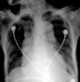

Tracheobronchial cartilage calcification